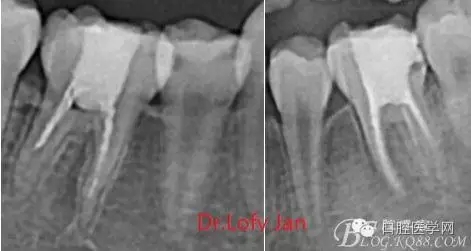

前言:自己做的一些曲面斷層片在未試尖根管治療中的病例整理,發(fā)現(xiàn)問題很多包括自身的,技術(shù)的,還有設(shè)備的問題,予以總結(jié)整理并期待進(jìn)一步提高。

根管治療術(shù)是牙體牙髓疾病治療中最復(fù)雜和最關(guān)鍵的治療項(xiàng)目。根管充填材料抵達(dá)根尖、并能嚴(yán)密堵塞根尖孔,是確保根管治療效果的關(guān)鍵指標(biāo)。為了保證根管充填到位,醫(yī)生需要在術(shù)前照牙片以了解牙根根管的數(shù)量、彎曲程度和長度,在術(shù)中有時(shí)需要插針照牙片來精確測量根管長度,術(shù)后必須照牙片以確定是否根管充填到位,如果欠填或超填,就需要重新充填、重新照牙片確認(rèn),直到根管充填到位。所以,在患者接受根管治療時(shí)有時(shí)會反復(fù)照牙片。

《數(shù)字化根尖片、曲面斷層片、CBCT測量牙齒長度準(zhǔn)確性的比較研究》文中顯示:平行投照數(shù)字化根尖片影像長度和牙齒實(shí)際長度之間無顯著性差異(P0.05);數(shù)字化曲面斷層片影像長度和牙齒實(shí)際長度之間有顯著性差異(P0.05),平均失真率為17.05%。CBCT冠狀面測量結(jié)果中除上頜前磨牙區(qū)、下頜前磨牙區(qū)與真實(shí)長度差異無統(tǒng)計(jì)學(xué)意義(P0.05)外,其余6個(gè)分區(qū)差異均有統(tǒng)計(jì)學(xué)意義(P0.05);矢狀面測量結(jié)果中上頜磨牙區(qū)、下頜磨牙區(qū)、下頜前磨牙區(qū)、下頜尖牙區(qū)、下頜前牙區(qū)與真實(shí)長度比較差異均有統(tǒng)計(jì)學(xué)意義(P0.05)。結(jié)論平行投照數(shù)字化根尖片較曲面斷層片和CBCT能更加精確地反映牙齒的真實(shí)長度。

病例分析:曲面斷層片在x線輔助診斷與檢查中目前大多數(shù)文獻(xiàn)和著作都建議只能作為初診拍片檢查手段,不能作為終末疾病的確診與手術(shù)療效的評價(jià)指標(biāo),臨床大部分中小型門診都因?yàn)樵O(shè)備不齊全導(dǎo)致信息偏差很大。